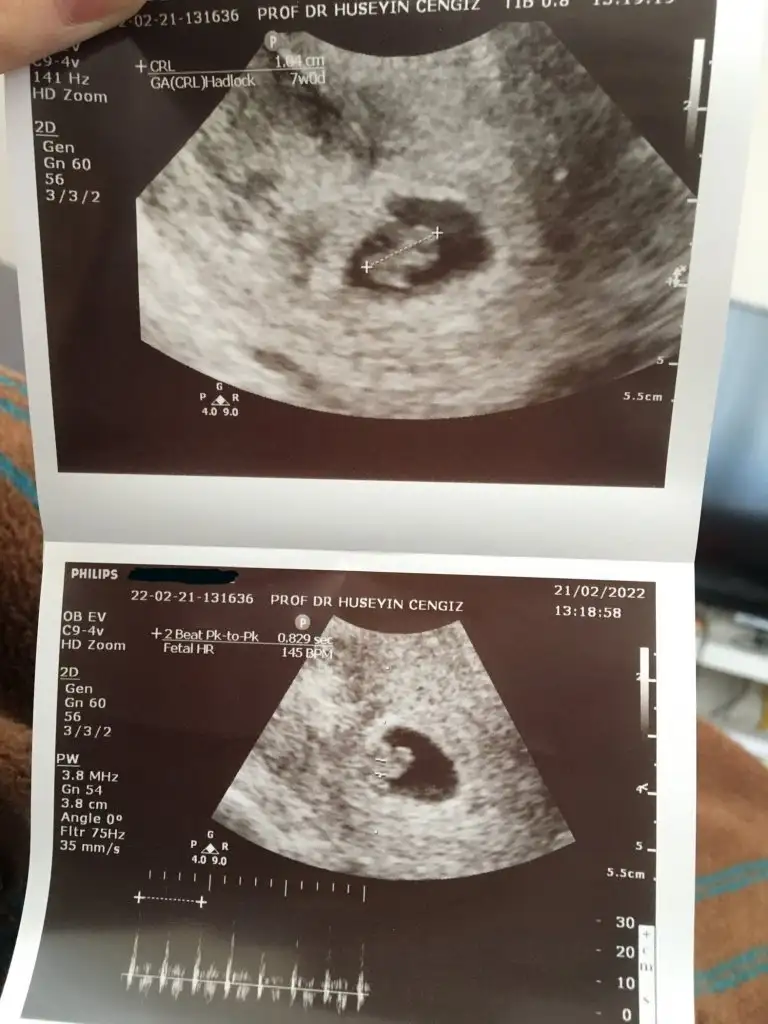

Hepsi vajinal ultrason.

Sırayla 6+5, 7+0, 8+6 hafta görüntüleri. Merakla yorumunuzu bekliyorum 🤩

5F5A868D-D889-45DC-A5F4-9B0753694059.webp

595F5D4B-6C39-4F72-98F6-1146AB445D16.webp

ABAEEA7E-612A-4234-A9CF-137C63FB60C1.webp